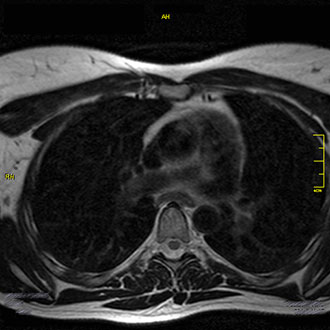

Die MRT des Brustkorbs (Thorax) ermöglicht eine strahlungsfreie Darstellung der Weichteile, Knochen und Gefäße im Brustbereich.

Im Kernspin Zentrum Köln führen wir ausgewählte MRT-Untersuchungen im Brustraum durch – insbesondere zur Beurteilung des Mediastinums und bei speziellen Fragestellungen des Brustkorbs.

Für die Darstellung des Mediastinums (Raum zwischen den Lungenflügeln) ist die MRT besonders geeignet.

Im Kernspin Zentrum Köln lassen sich mit der MRT sowohl das vordere als auch das hintere Mediastinum exakt abbilden.

Die MRT ermöglicht hier eine präzise und strahlungsfreie Diagnostik der Weichteile, Gefäße und angrenzenden Strukturen.

Eine MRT des Brustkorbs kann im Kernspin Zentrum Köln bei speziellen Fragestellungen sinnvoll sein.

Die MRT Brust im Kernspin Zentrum Köln bietet eine präzise und sichere Diagnostik im Bereich des Brustkorbs, insbesondere des Mediastinums.